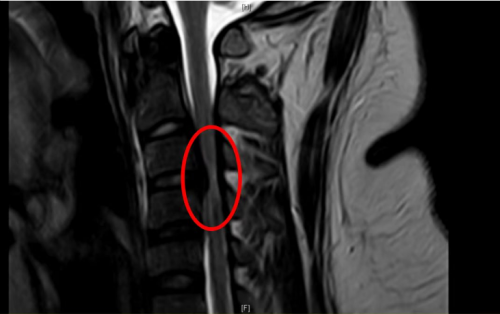

标红部位提示颈椎椎管狭窄、脊髓受压变性

“患者体重高达320斤,属于重度肥胖,且合并高血压,经过完善核磁检查,诊断为脊髓型颈椎病、颈椎椎管狭窄、颈椎后纵韧带骨化,由于病情严重,已经造成颈椎椎管狭窄、脊髓受压变性。”立博体育|实时赛事直播与比分|权威专家分析与体育竞猜平台